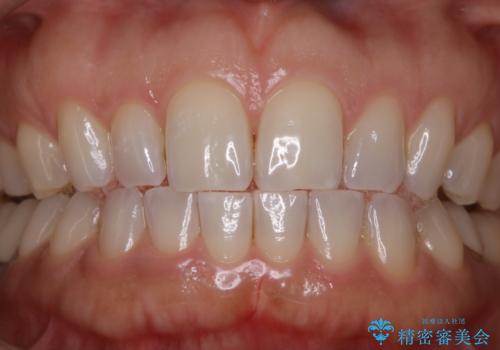

エアーフロー+オフィスホワイトニング

- 3カ月に1度、メンテナンスとしてエアーフローとオフィスホワイトニング来院されてます。

スペシャルコースのオフィスホワイトニングをされていますが、初めの1回はエクセレントコースをされてます。

現在は白さをキープする為、スペシャルかスタンダードコースにしています。

エアーフロー後のオフィスホワイトニング

エアーフロー後のホワイトニングは、バイオフィルムやぬめりがなく、ホワイトニング剤が吸収しやすく、セットで行うことをおすすめします。